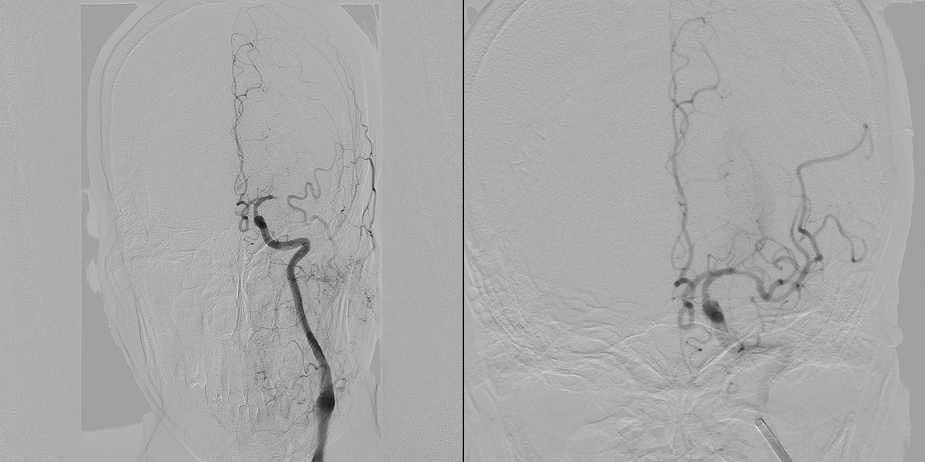

六、典型急诊取栓病例病例一:患者为56岁男性,既往有脑梗死病史,因“右侧肢体无力半天”到我院急诊就诊。急诊颅脑MR提示后循环多发急性脑梗死、基底动脉闭塞,有紧急行急诊取栓治疗的指征,患者家属签字同意行急诊取栓治疗,术中证实后循环大血管闭塞,神经内科介入医生采用支架取栓术获得良好的再通血流,术后复查颅脑MR提示梗死体积较前增大不明显,患者四肢肌力恢复正常。

急诊取栓术前造影(左)、急诊取栓术后造影(右)